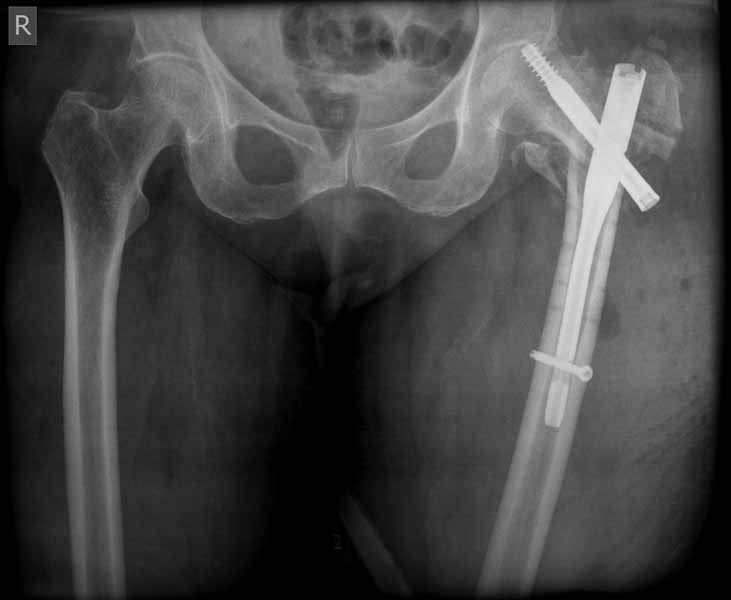

Прилагаю снимок сделанный еще в стационаре через 2 недели после операции.

Да, согласен, в такой же репозиции Гамма был бы таким же несостоятельным фиксатором. Проблема в репозиции медиального кортекса, который судя по снимку на месте и опора есть, а на самом деле не так. Как можно его проконтролировать? Дигитально, указательным пальцем пробраться через рану и пощупать? Иногда можно так репонировать перелом шурупом DHS - щупать пальцем язык перелома, который часто около малого вертела и можно до него достать пальцем и при малом разрезе, и поворачивая шуруп еще закручивая его на рукоятке репонировать перелом когда шуруп начнет брать кость. Если остеопороз не сильный и шуруп берет сразу, можно поставить антиротационный шуруп при репонированном положении перелома.

Проблема в репозиции медиального кортекса

При переломах типа A2 - с фрагментированием медиальной стенки - не получится ее репозиция никогда, что ж теперь, остеосинтез не делать?

Проблема основная тут в остаточном варусе. Даже если отломки по медиальной стенке при этом окажутся в контакте, от cutout это не спасет. Плюс короткий винт, еще и эксцентрично расположенный, так что совсем мало кости ему резать надо.

А так - чем более оскольчатый и дистально распространенный перелом, тем больше выбор склоняется к гвоздю. Но и он не спасет, если основные отломки оставить в варусе.

Первые снимки показывают технические погрешности установки DHS. Не была достигнута репозиция, конечность в флексии и шейка в ротации. Сегодня все меньше обращают внимание на параметры для оценки репозиции (S контуры Lowell в обеих проекциях и Garden Alignment Index, в норме 155 и 180 градусов), хотя такие простые тесты помогли бы дорепонировать смещение. Винт находится сзади в головке, что при нагрузке поменяет вектор и вместо компрессии в линии перелома срежет головку-Cut Out!

В зависимости от дистанции линии перелома и латерального кортекса надо использовать разной длины barrel, т.е. конец баррели не должен доходить до пределов перелома. Здесь конец длинного ствола упирается в медиальный фрагмент, что мешает созданию компрессии, а более короткий barrel создал бы запас для компрессии. В боковой пластине вместо 4х можно было ограничится двумя шурупами, потому что головка шурупа в 4.5 мм выдерживает давление до 350 кг.

Вторая операция- это фаза сохранения головки бедра. Желательно приложить все усилия и сохранить головку, но, как видно, “фиаско” продолжается. Здесь вместо нейтрализации сил между медиальной и латеральными сторонами была попытка удержать варус. Варус не удержать ни деротационными шурупами о котором говорили и не костными стружками вбитые в шейку, потому что вся нагрузка упирается в головку.